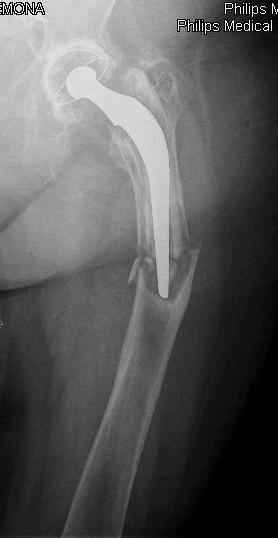

Hello! This is just illustration in one of the choice of treatment

Michael